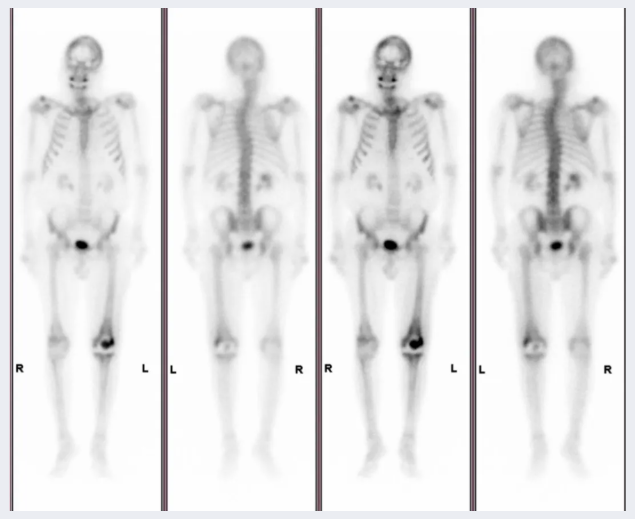

甲状腺显像

▲左为正常甲状腺,右为甲状腺“冷结节”

了解甲状腺的位置、形态、大小及功能状态;异位甲状腺的诊断;甲状腺结节的功能状态的判定;协助诊断甲亢、甲减、甲状腺炎等疾病;颈部包块与甲状腺关系的鉴别;术后残余组织再生修复情况;甲状腺亲肿瘤显像用于腺体内包块良恶性鉴别;甲状腺癌及转移灶的诊断。